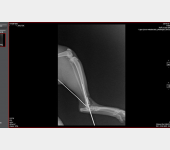

Kajtek nie miał łatwego życia. Znaleźliśmy go w pudle. Był w dramatycznym stanie. Najmniejszy i najsłabszy że stada... a mimo to najbardziej się łasił i lgnął do człowieka. Przez koci katar pękło i wypłynęło mu oczko. Wymagał opieki, zakraplania, masowania. Postanowiliśmy, że zostanie u nas, w domu tymczasowym, na stałe. Kiedy podrósł wymagał dwóch operacji: oka oraz migrującego jądra. Przeszedł je całkiem niedawno. Teraz znów uległ wypadkowi...

Koszt to 1500zł + wizyty, leki, pobyt w klinice, badania i prześwietlenia... My prosimy chociaż o 500. Wiemy, że siła tkwi w dobrych ludziach.